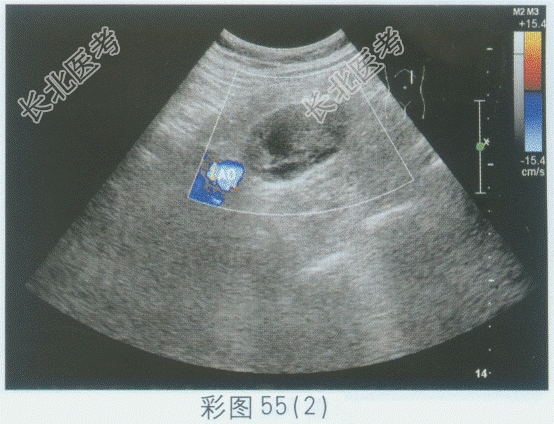

超声综合描述: 左肾下极与腹主动脉之间可见不均质低回声,与腹主动脉关系密切, 边界清晰,形态规则, 内可见形态不规则无回声,CDFI: 其内及周边均未见动静脉血流信号。见下图及彩图55。

超声提示: A、腹膜后囊实性占位(神经鞘瘤)